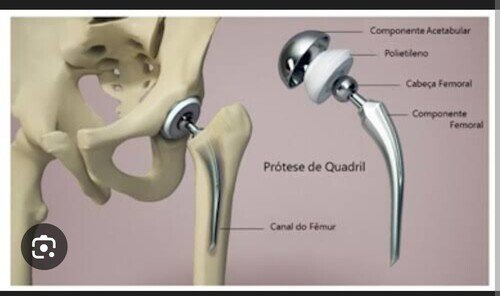

Prótese de fêmur para Marlucio Benevides

Sou esposa de Marlucio, criei essa vakinha para arrecadar uma contribuicao beneficiente para a compra de uma protese de fêmur para Marlucio Benevides Das Neves, ele foi diagnosticado com astrose a 2 anos,agradeço a ajuda de todos! ver tudo

Sou esposa de Marlucio, criei essa vakinha para arrecadar uma contribuicao beneficiente para a compra de uma protese de fêmur para Marlucio Benevides Das Neves, ele foi diagnosticado com astrose a 2 anos,agradeço a ajuda de todos!